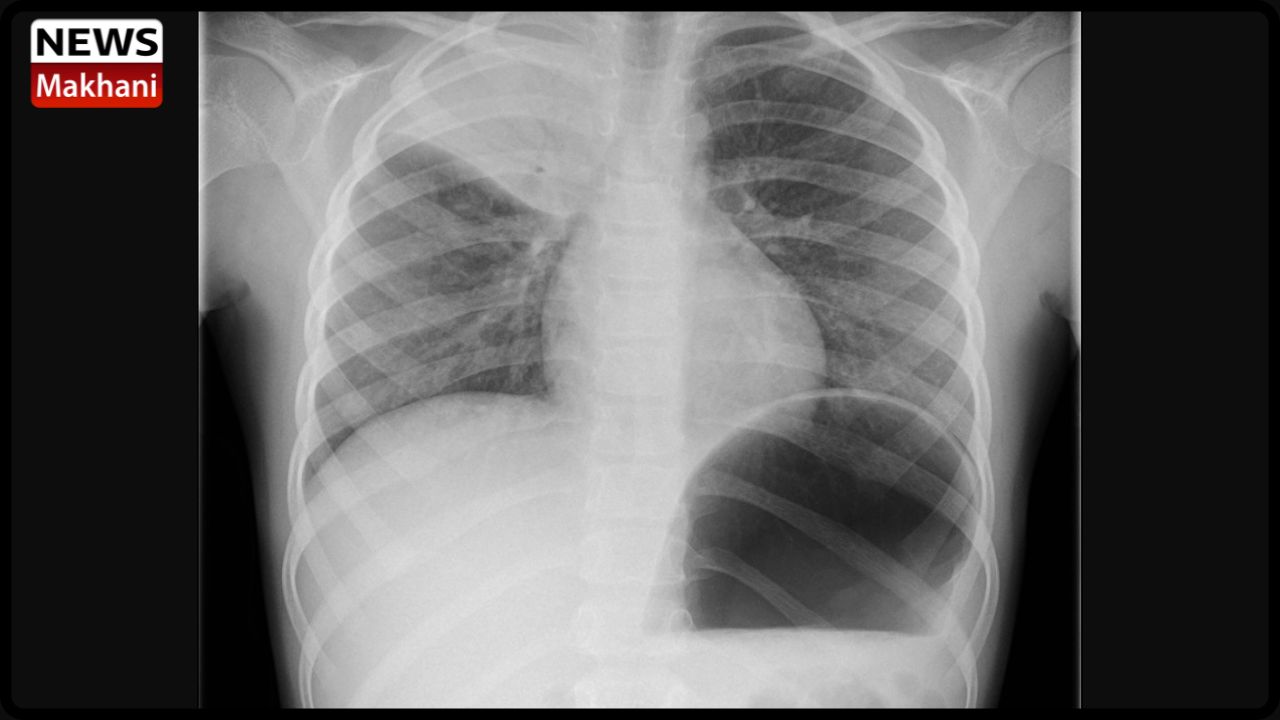

Children’s Pneumonia Diagnosis Pneumonia in children can be identified through physical examination, unusual breathing patterns, and a lungs-only listen. Blood tests and chest X-rays are also done to determine whether the youngster has pneumonia. It can sometimes be possible to tell if a child has pneumonia by monitoring how many breaths they take in a minute.